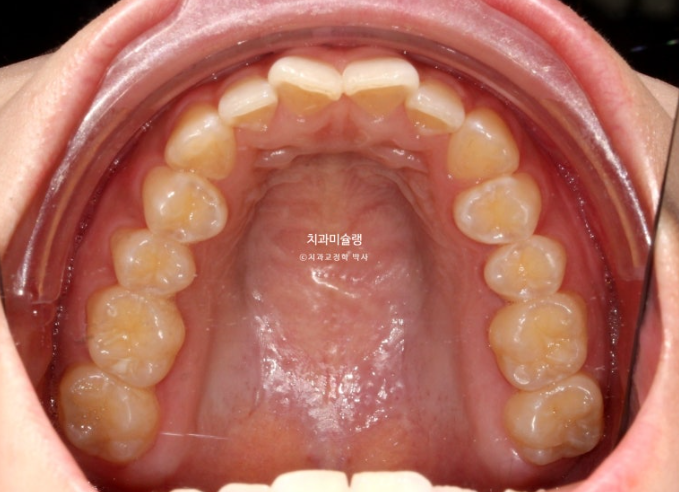

선수술 후 한달간의 회복기를 거쳐 25년 1월 본원에 내원했을 때의 교합 상태입니다.

25.01

앞니 두 개는 나비치아 돌출이며

어금니 교합이 떠있습니다.

앞니에 배열이 삐뚤합니다.

이 정도의 상태라면 14개 장치 안에서 해결이 가능합니다.

즉 인비절라인 라이트로도 충분합니다.